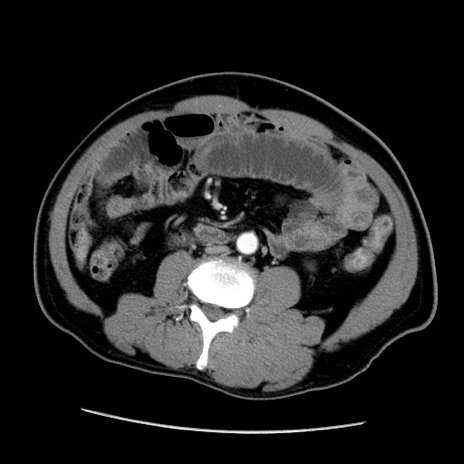

症例22(横断像)

【症例】50歳代男性

【主訴】腹痛

【現病歴】AVMからの被殻出血のため回復期リハ病棟入院中。 本日午後3時頃急に下腹部痛が出現した。

【既往歴】AVM、被殻出血、虫垂炎、高血圧

【身体所見】意識晴明、左半身不全麻痺、会話の理解は良好、36.5°C、腹部:膨隆、全体に板状硬、下腹部正中に圧痛点あり、反跳痛-、筋性防御不明、右下腹部にope scar

【データ】WBC 9400、CRP 0.06